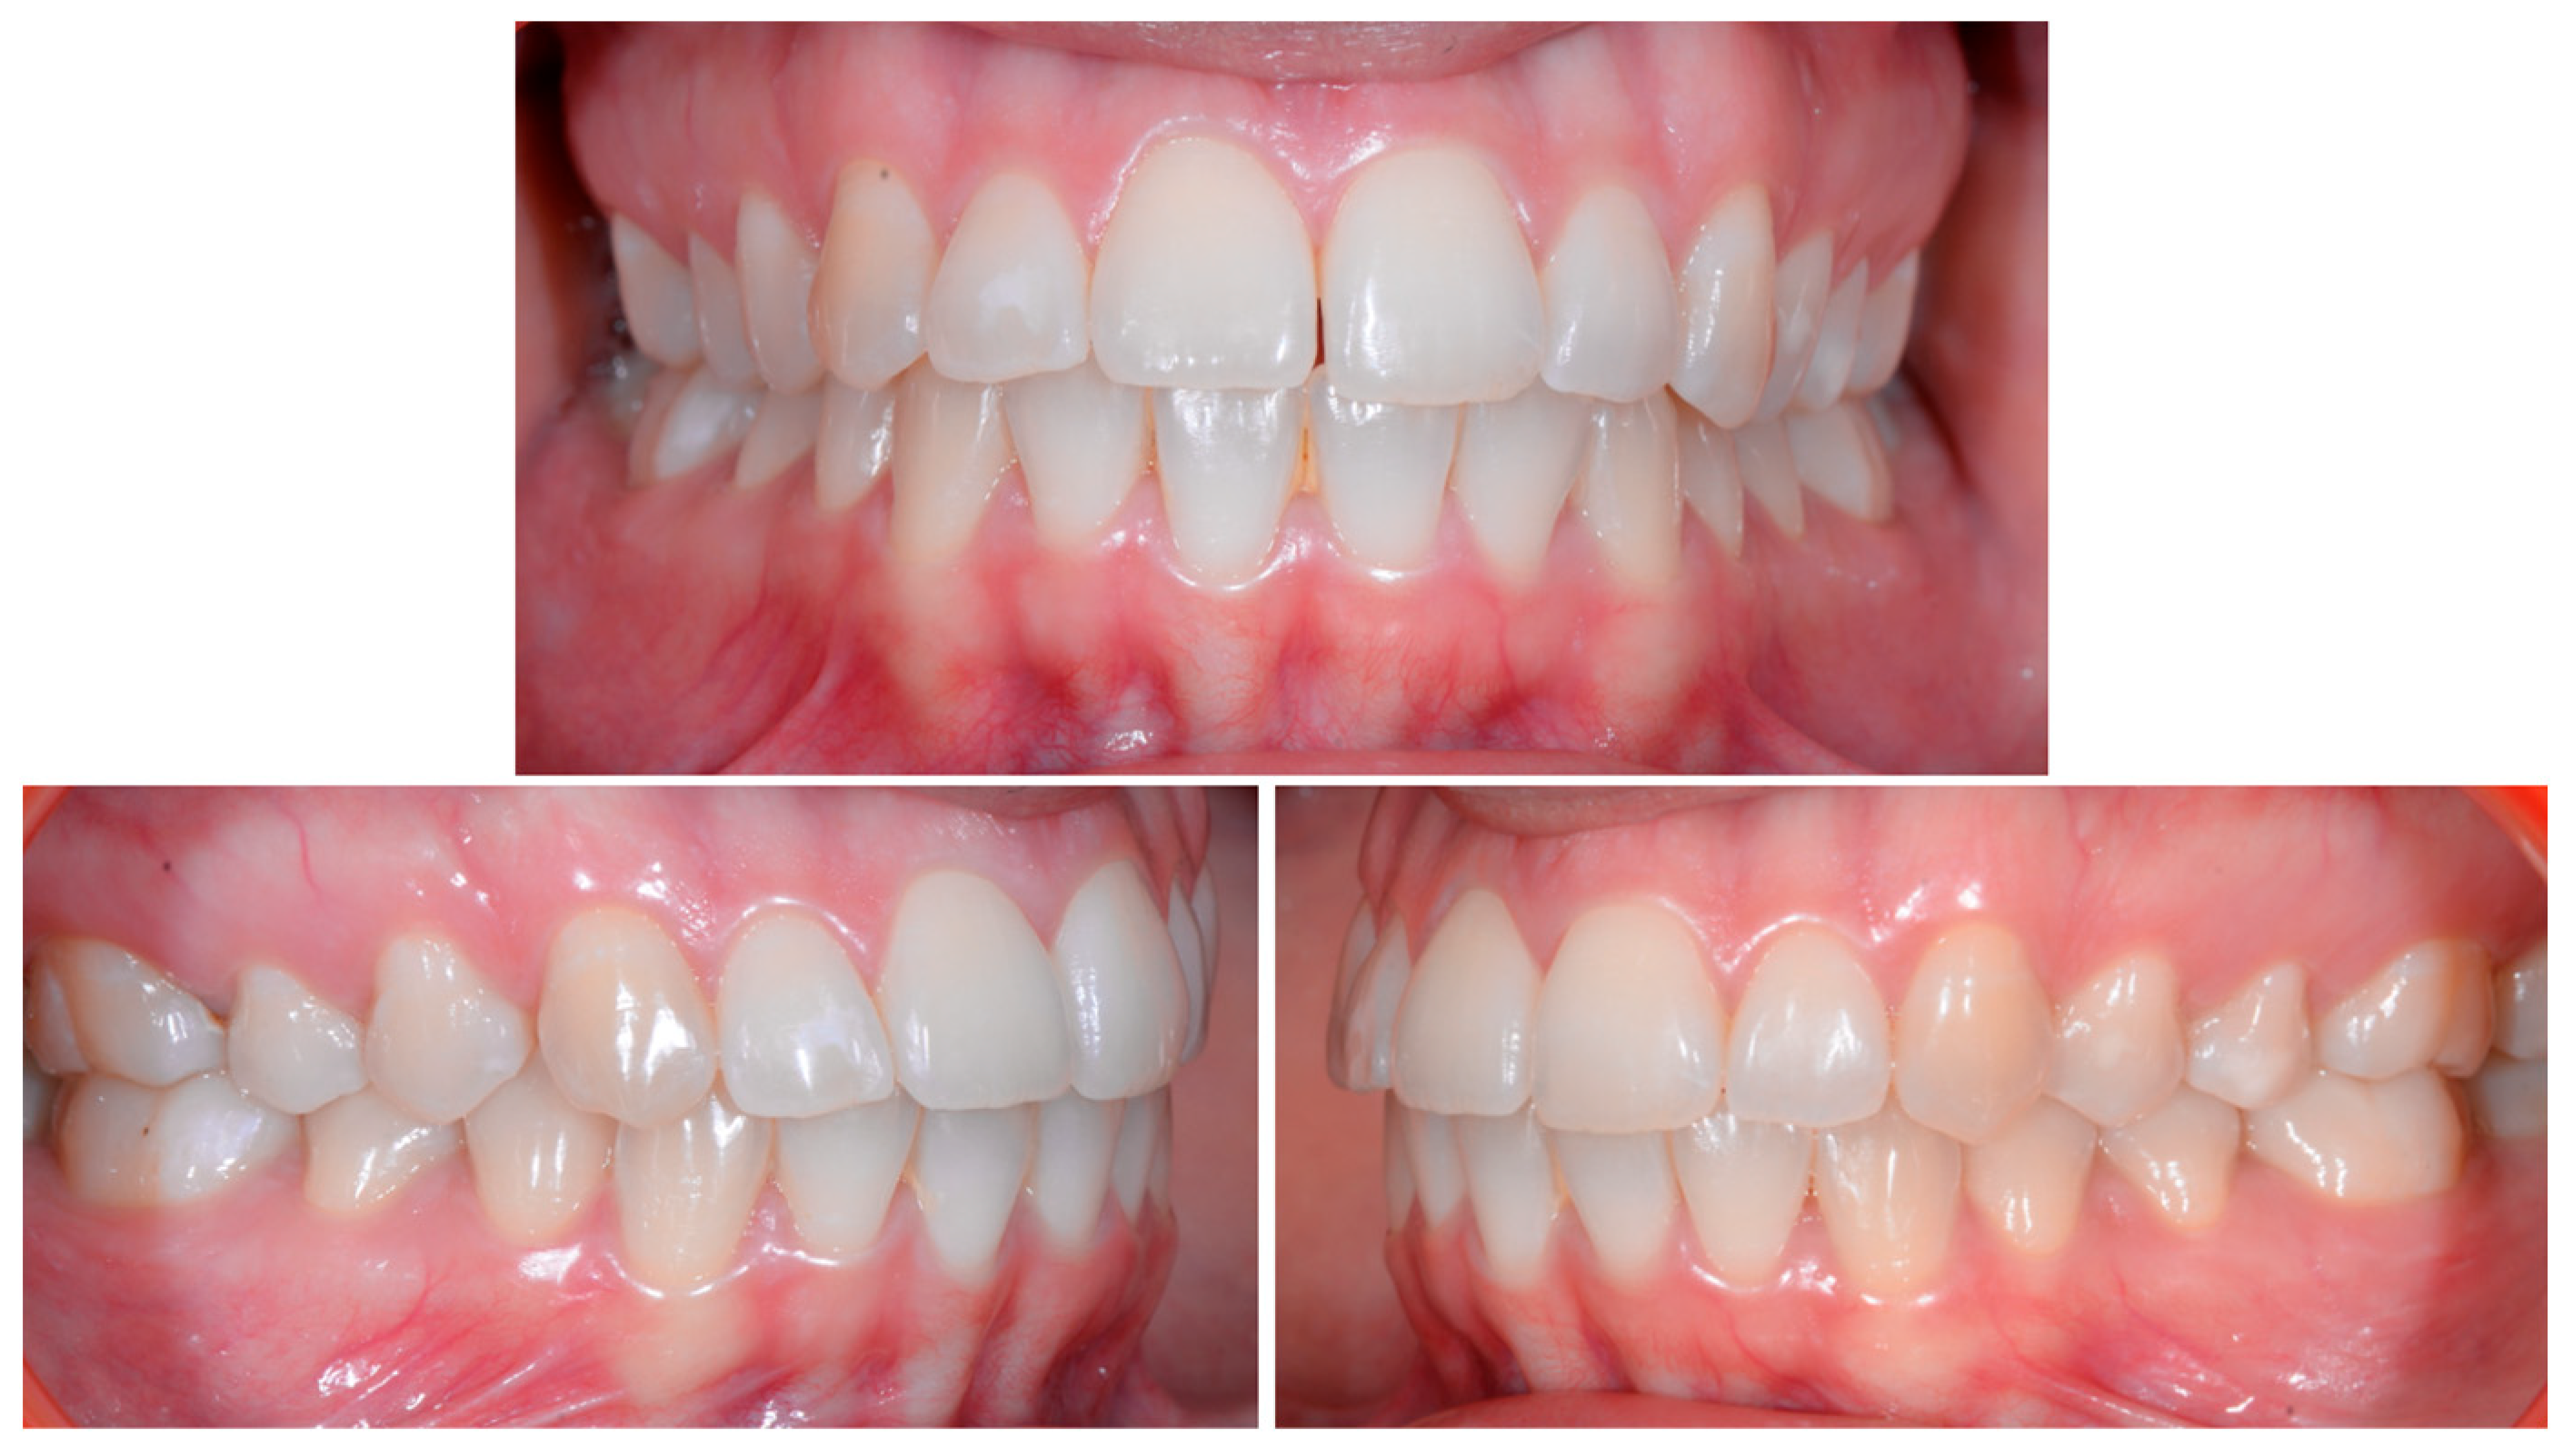

A 26-year-old female patient was referred by her general dentist for suspected wire syndrome. Orthodontic treatment had been performed 10 years previously, and bonded restorations had been fitted at the end of the treatment. The patient mentioned several episodes of breakage/adhesion, without further details. She has good oral hygiene and a right and left Class I (Figure 5).

Figure 5.

Intermediate wire syndrome. Frontal and lateral views.

In Figure 6, 11 and 21 show a difference in incisal edge height and gingival margin. Tooth 41 shows gingival recession to the muco-gingival junction (Cairo’s RT1) with root visibility. Tooth 33 had a significant lingual tilt (coronal–lingual torque), not symmetrical to tooth 43.

Figure 6.

Intermediate wire syndrome. Frontal view.

The root of tooth 21 is visible through the gingiva (Figure 7). Figure 8 shows the extent of gingival recession on tooth 41.

The occlusal views provide additional relevant information (Figure 9 and Figure 10). A maxillary retainer was present on 11 and 21 only and a difference in visibility of the vestibular surfaces (differential torque) on these same teeth was noted.

Figure 9.

Intermediate wire syndrome. Occlusal view.

Figure 10.

In the mandible, the retainer was broken distal to 42 and, despite being intact on 33, this tooth had increased visibility of its vestibular surface compared to its contralateral tooth (differential torque). Finally, teeth 31 and 41 also showed a difference in the visibility of their vestibular surfaces (differential torque). Ultimately, the patient was diagnosed with an X-effect wire syndrome on 21, an X-effect wire syndrome on 41, and a Twist-effect wire syndrome on 33.